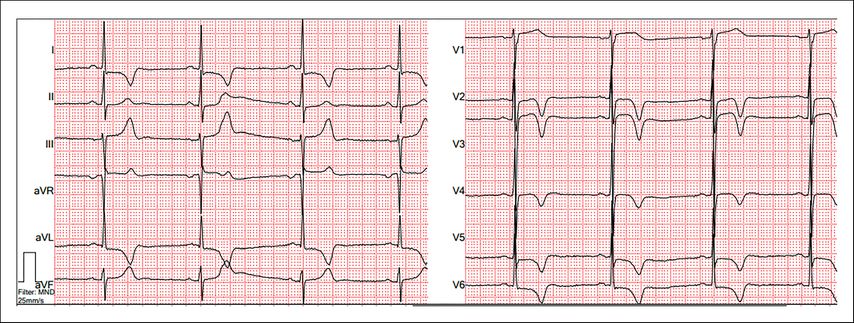

Einen Hinweis auf das Vorliegen eines verdickten Herzmuskels kann das EKG geben. Tiefe S-Ausschläge über V1/2 und überhöhte R-Zacken in den lateralen Ableitungen sind typisch. Hierüber können der Sokolow-Lyon-Index oder der Lewis-Index bestimmt werden. Ebenfalls sehr etabliert sind die Cornell-Kriterien oder die Bestimmung des Cornell-Produkts, in das auch die Dauer des QRS-Komplexes einfließt. Auch weitere Beurteilungskriterien, wie die Peguero-Lo-Presti-Kriterien, sind in der Literatur beschrieben, allerdings in der klinischen Routine weniger etabliert. Gemein ist allen EKG-Kriterien eine niedrige Sensitivität bei moderater Spezifität, weshalb ein solcher Hinweis immer auch eine Bildgebung nach sich ziehen sollte.7 Auch eine Achsenabweichung nach links und typische Veränderungen der ST-Strecken und T-Wellen in den präkordialen Ableitungen können hinweisgebend sein (Abb.1).

Abb. 1: EKG bei HCM/HOCM mit positivem Sokolow-Lyon-Index und sekundären Repolarisationsstörungen

Bei ATTR-Amyloidose fehlen diese typischen Kriterien häufig. Das EKG kann eine paradoxe Niedervoltage, ein Pseudoinfarktmuster mit Q-Zacken und eine träge R-Progression zeigen.